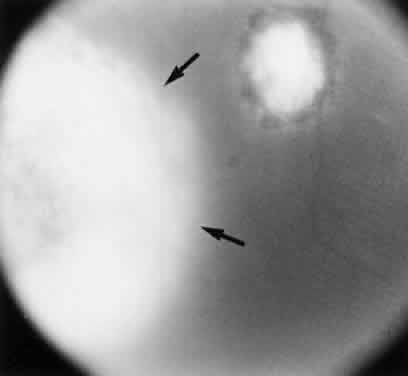

Fig. 2. Toxoplasma bradyzoites inside cysts of tissue sections in chronically infected rabbit's retina (arrows). The animal was killed 6 months after acute Toxoplasma retinochoroiditis after suprachoroidal injection of 1000 organisms (Beverley strain). There was no clinical evidence of inflammation at the time of killing. (H & E, × 400)

Fig. 3. Toxoplasma cysts containing bradyzoites in a human retina (arrows). The eye was enucleated because of absolute glaucoma. The patient had been treated with oral and periocular corticosteroids. (H & E, × 400)